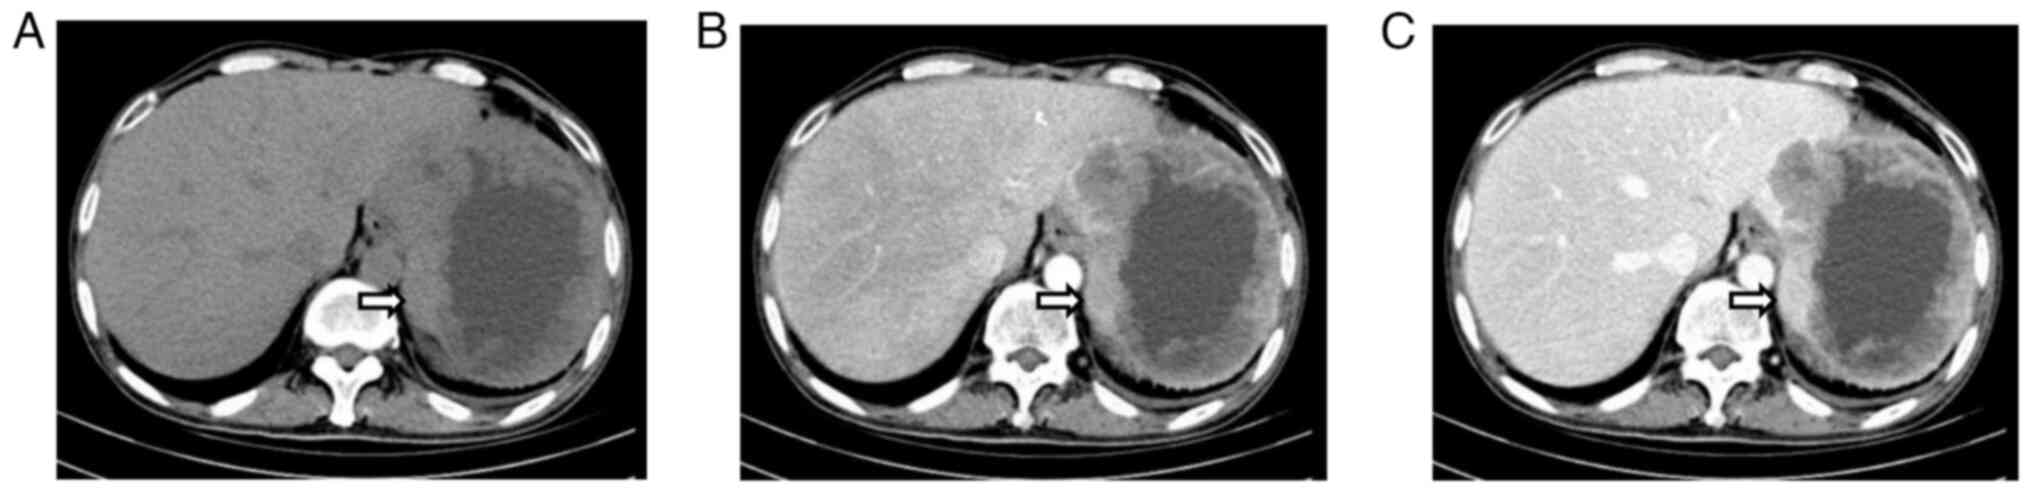

A subsequent computed tomography (CT) scan confirmed the presence of an abdominal mass (Fig. 2). An abdominal plain CT scan detected an irregular soft-tissue mass measuring 125.9×101.3 mm with an irregularly thickened wall in the residual spleen (Fig. 2A). The mass showed uneven enhancement in the arterial phase (Fig. 2B) and no obvious regression in the delayed phase (Fig. 2C). Imaging examinations, such as CT scans (Fig. 3) of the brain, lungs and abdomen, together with US of the liver, gallbladder and pancreas were performed. There were no metastases in the lungs (Fig. 3A), the liver (Fig. 3B), the lymph nodes in the upper abdomen (Fig. 3C), the pancreas (Fig. 3D and E) or the brain (Fig. 3F). A bedside percutaneous splenic mass biopsy was next performed under US guidance (Fig. 4).

Figure 2.

Abdominal CT plain and enhanced scan. (A) A CT plain scan detected an irregular soft-tissue mass (arrow) in the residual spleen, irregular thickening of the wall and a low-density effusion shadow. (B) After contrast agent injection, slight uneven enhancement was found in the peripheral solid thick wall and no enhancement in the inner area during the arterial phase. (C) The mass exhibited mild low enhancement in the peripheral solid thick wall during the delayed phase, and no obvious regression was found. CT, computed tomography.